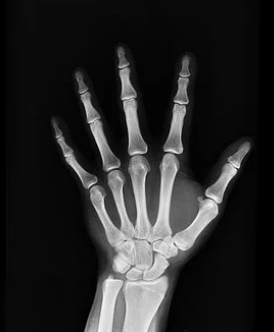

보통 성장판은 손목이 가장 빨리 닫힙니다. 일반적으로 성장판 닫히는 순서는 손목, 어깨, 팔꿈치, 무릎, 발목, 손가락, 발가락 뼈들입니다.

그러나 손목이 아닌 아직 다른 곳이 열려있다면 아직 키가 클 가능성이 충분히 있죠. 그중에서 최종키를 결정짓게하는 가장 중요한 성장판은 발목이나 무릎의 성장판입니다.

급성장기에는 성장판 검사를 통해 우리 아이 골연령의 속도가 빠른지, 느린지 급속도로 빨라지지는 않았는지 체크가 필요합니다.